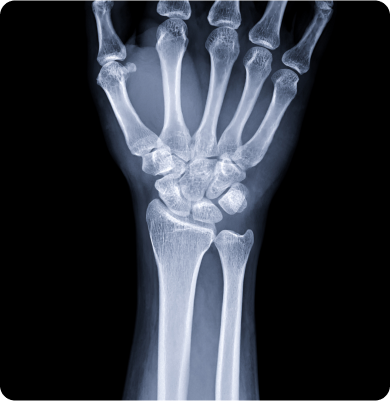

손목의 신경이 압박을 받아 발생하는 질환

반복적인 손목 움직임이나 과도한 압박, 장시간의 손목 사용 등이 주요 원인으로 특히 컴퓨터 작업이나 스마트폰 사용 등에서 발생할 수 있습니다.

손목의 새끼손가락 쪽 관절을 지지하는 삼각섬유연골복합체가 손상되거나 파열되는 질환

넘어지면서 손을 짚는 외상, 손목의 반복적인 회전 동작, 테니스나 골프처럼 손목을 많이 쓰는 스포츠 활동 등이 원인입니다.

관절내시경 수술, 수근관유리술, 활차 유리술, 관절경 건유리술

스테로이드 주사치료, 프롤로테라피 주사치료, 초음파 가이드 주사치료, 체외충격파 치료